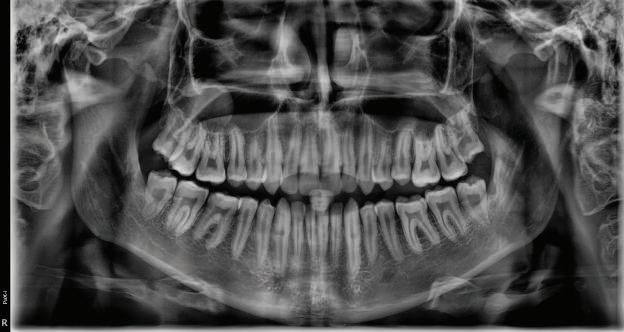

Dental Tribune Bulgarian Edition / октомври 2022 г.16 клиничен случай с алайнери Г орният латерален ре зец е вторият найчесто вродено липсващ зъб.1,2 Поради разполо жението му във видимата зона на усмивката лечение то на подобни случаи нала га мултидисциплинарен под ход, целящ отличен функцио нален и естетичен резултат. Налице са няколко лечебни мо далности, свързани с различ но разпределение на място то: първият вариант е орто донтско отваряне на място и възстановяване на липсва щия зъб с конструкция, под държана от съседните зъби3 или от имплант4, докато при втория подход разстоянията се затварят и премоларът заема мястото на канина.5 Изборът на лечебен подход трябва да бъде направен съв местно от зъболекар и паци ент въз основа на очакванията на последния и предвиди мостта на лечението. Множе ство фактори влияят върху това решение, като напри мер типа малоклузия, размера, формата и цвета на кучеш ките зъби6, оклузалните вза имоотношения (овърджет и овърбайт), лицевия профил, дължината на зъбната дъга и несъответствията в разме ра на зъбите.7 В настоящата публикация се разглежда случаят на жена в зряла възраст с вродена лип са на горен ляв латерален резец. Бяха приложени про зрачни алайнери за отваряне на място за единичен им плант и бяха постигна ти функционална оклузия и отлична естетика. ПРЕДСТАВЯНЕ НА СЛУЧАЯ Диагноза Пациентката бе на 32 годи ни, когато лечението започна, и първоначалното ѝ състоя ние бе следното (фиг. 1–3): липсващ горен ляв латерален резец; клас II, подклас I малоклузия; отклонение на горната сре динна линия вляво; Доклад на клиничен случай ЛЕЧЕНИЕ С АЛАЙНЕРИ НА ПАЦИЕНТ С АГЕНЕЗИЯ НА ЛАТЕРАЛЕН РЕЗЕЦ Д-р Iro Eleftheriadi и д-р Christodoulos Laspos, Гърция и Кипър Фиг. 1a–h Предоперативни лицеви и интраорални снимки. Фиг. 2a–e Дигитални модели преди началото на лечението. Фиг. 3 Панорамна снимка преди лечението. Фиг. 1a Фиг. 1d Фиг. 1f Фиг. 2a Фиг. 2d Фиг. 2b Фиг. 2e Фиг. 3 Фиг. 2c Фиг. 1b Фиг. 1e Фиг. 1g Фиг. 1h Фиг. 1c

Dental Tribune Bulgarian Edition / октомври 2022 г. 17клиничен случай с алайнери леко струпване в долната че люст; несъответствие по Болтън (мандибуларен излишък от 3.06 мм във фронталната зона и общо 1.47 мм); издължено лице с лицева аси метрия; конвексен профил с ретруди рана долна челюст и проми нентен нос. На мястото на зъб #46 бе на лице имплант, а зъби #16 и 26 са ендодонтски лекувани. Тези зъби бяха асимптоматич ни, затова бе взето решение да се прави релечение само при нужда. Мъдреците липсваха. Анализът на телерентгеногра фията (фиг. 4) показа ретрог натна мандибула (SNB: 74.2°) и нормална инклинация на резците както в

Цели на лечението и лечебен план Целите на лечението бяха следните: нивелиране и подреждане на зъбите и в двете зъбни дъги; отваряне на пространство за липсващия латерален резец; коригиране на отношенията при канините и моларите до клас I; и корекция на отклонението на срединната линия. Лечебният план включваше: корекция на отношенията при кучешките зъби и мола рите до клас I с дистализира не на максилата; отваряне на пространство в областта на #22 за поставя не на единичен имплант; корекция на срединната ли ния; и създаване на място за раз ширяване на зъб #12 и апрок симална редукция в долната челюст с цел подобряване на несъответствието по Болтън и осигуряване на подобра оклузия. Изпълнение на лечебния план Този случай бе изпълнен със системата за алайнери Invisalign (Align Technology). Одобреният първоначален лечебен план предвиждаше 49 алайне ра с дистализиране на задни те горни зъби до клас I (прибли зително с около 3.5 мм; фиг. 5). За бъдещия имплант в областта на липсващия латерал бе планирано пространство от 6.5 мм, докато във фронталния сегмент на долната челюст бе предвидена апроксимална редук ция. В дясната страна бутон за ластици клас II бе поставен на зъб #47 вместо на зъб #46, за да не се увреди короната на импланта. Понеже пациентката жи вееше в чужбина,

следните казуси: недобра оклу зия в дисталните зони по вре ме на дистализирането на гор ната челюст и накланяне на зъб #21 (фиг. 7). Последното се дължи на липсата на компози тен атачмънт на този зъб, каквото не бе зададено в пър Фиг. 4 Телерентгенография и цефалометричен анализ преди началото на лечението. Фиг. 5a–e Одобреният първоначален лечебен план. Фиг. 6a–h Снимки по време на лечението, показващи нуждата от внасяне на някои корекции. Фиг. 4 Фиг. 5a Фиг. 5d Фиг. 6a Фиг. 6d Фиг. 6f Фиг. 6b Фиг. 6e Фиг. 6g Фиг. 6h Фиг. 6c Фиг. 5e Фиг. 5b Фиг. 5c

Dental Tribune Bulgarian Edition / октомври 2022 г.18 воначалния план. Тези пробле ми бяха адресирани чрез допъл нителна поръчка на алайнери с торк контрол и зададено екст рудиране на задните зъби с цел установяване на добри оклузал ни контакти в дисталните об ласти, като бяха предвидени и оптимизирани атачмънти с контрол над корените за корекция на ангулацията на макси ларните резци (фиг. 8). Резултати от лечението Панорамната рентгено графия след ортодонтското лечение показа благоприятна паралелна позиция на съседни те зъби, подходяща за поставя не на имплант в областта на #22, както и конвергенция на ко рените на зъби #44 и 45 (фиг. 9), но преценихме, че няма да от деляме допълнително лечебно време за коригирането ѝ поради факта, че пациентката бе мно го доволна от постигнатия до момента резултат. След при ключване на лечението бяха постигнати отлични взаимо отношения клас I при мола рите и канините, а срединни

(LFH: 56.5 mm) и размерите на меките тъка ни останаха непроменени. На клонът на горните резци бе за пазен (Ui–FH: 115.8°), а долните резци бяха леко наклонени ве стибуларно (Li–APog: 30°; фиг. 16). ДИСКУСИЯ Липсата на зародиш на по стоянен горен латерален резец е налице при 3.5–6.5% от евро пеидната раса, като при жени е по-честа, отколкото при мъ жете в съотношение 3:2.8–10 Възможни са няколко лечебни подхода, включително замя ната му с преоформен канин, отваряне на място чрез орто донтско лечение и протетич но възстановяване, както и ав тотрансплантация. Устано вено е, че изборът за затваря не на място или за отваряне то му все още подлежи на дис кусия сред ортодонти и проте зисти.11,12 Според литературните дан ни затварянето на простран ството и замяната на липсва щия латерал с канин се предпо чита в случаи на едностранна липса на зародиш, балансиран профил, кучешки зъби и премола ри със сходна форма и цвят, дву челюстна протрузия или клас II малоклузия.13–15 Отваряне на пространство по-често се изби ра при клас I, наличие на диасте ми и треми в горната зъбна дъга или голяма разлика в размерите на канини и премолари.16 Скорошно проучване е уста новило, че изборът на лечение при конгенитално липсващ ла терал е пряко свързан със след ните фактори17: възрастта на пациента при започване на лечението; индивидуалните особености при всеки конкретен случай; и сътрудничеството между специалистите в лекуващия екип. Макар да има проучвания, фа воритизиращи леченията със затваряне на място11,18, всеки случай трябва да бъде оценяван индивидуално. В презентирания в тази статия случай бе взето решение за отваряне на мяс то и протетично възстановя ване, понеже целта бе да се по стигнат клас I отношения при канините и моларите, както и по-широка усмивка. За да се из бегнат компромиси, след лече нието бе постигнат клас I при моларите и кучешките зъби, несъответствието по Болтън бе подобрено и срединната ли ния бе коригирана. Други изслед вания демонстрират отлични естетични и функционални ре зултати при лечение с отваря не на място и протетична ре хабилитация.19 И двете лечеб ни модалности са подходящи за третиране на вродена лип са на зародиш на латерал и да ват сходни функционални и па родонтални резултати20, като при едно проучване

ти и клас II ластици е устано вено, че осигурява достатъч на дистализация без промяна на лицевата височина.23 Както се видя от цефалометричния анализ, точно това бе постиг нато и в представения случай като се има предвид, че лице вата височина остана същата като първоначалната. Предвид леката тенденция към дистал Фиг. 8a–e Поръчаните допълнителни алайнери. Фиг. 9 Панорамна рентгенография след края на лечението. Фиг. 10a–c Странични (а и с) и фронтална интраорални снимки след края на ортодонтското лечение и поставянето на импланта (b). Зъб #12 все още не беше протезиран. Фиг. 11а и b Оклузални снимки след ортодонтското лечение. Фиг. 7a Фиг. 8a Фиг. 7d Фиг. 8d Фиг. 9 Фиг. 10a Фиг. 10b Фиг. 10c Фиг. 11bФиг. 11a Фиг. 7b Фиг. 8b Фиг. 7e Фиг. 8e Фиг. 7c Фиг. 8c Фиг. 7a–e Интраоралната ситуация по време на лечението. клиничен случай с алайнери

но